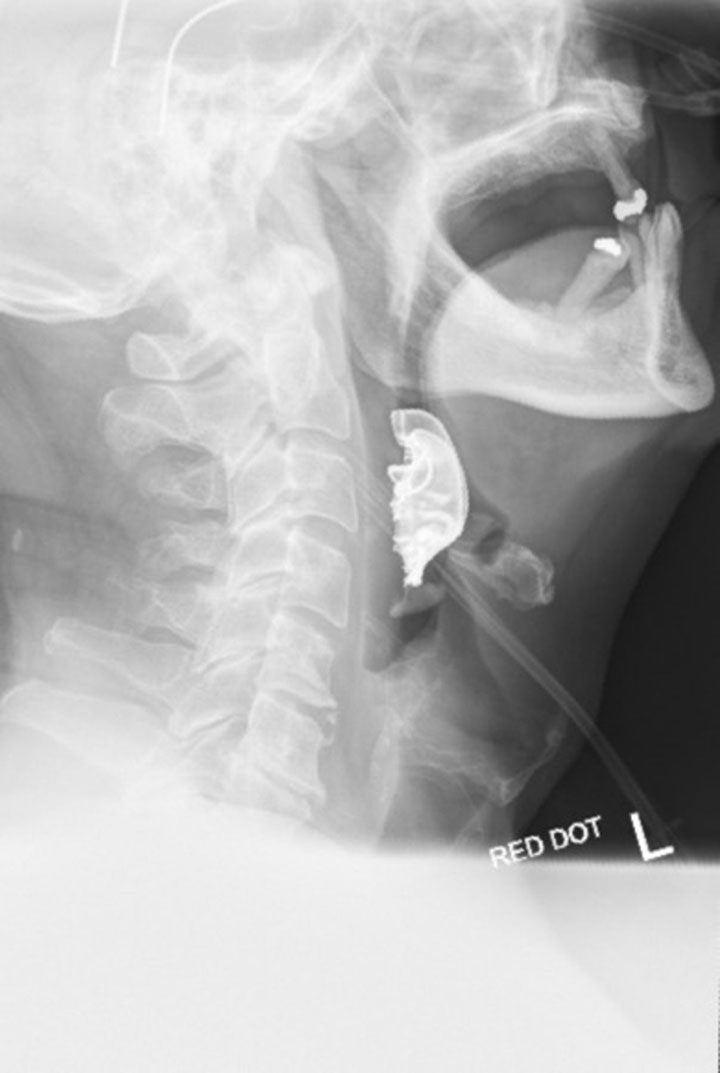

A neck X-ray showing a man’s dentures caught in his throat. BMJ Case Reports